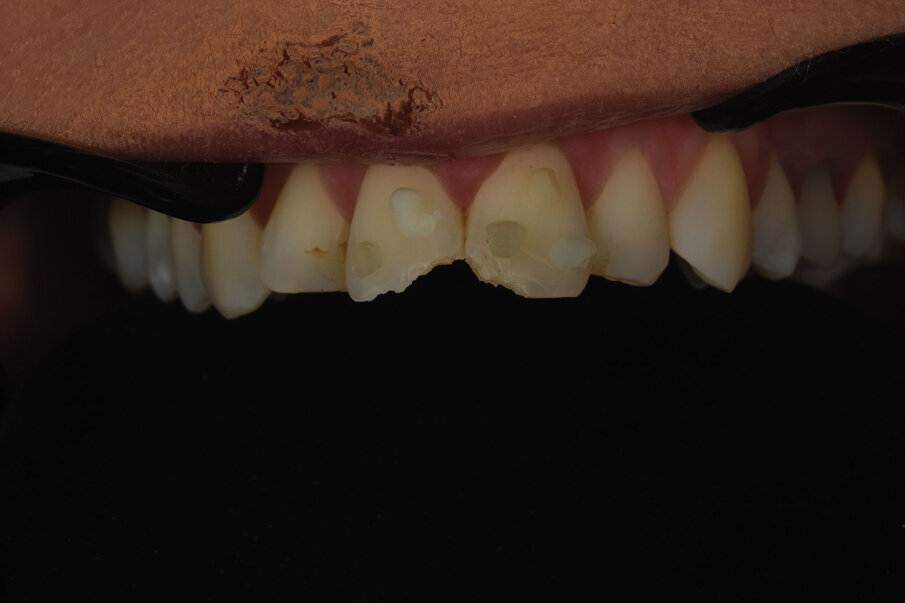

Sl. 1: Inicijalna situacija. Fraktura gornjih centralnih inciziva sa povredom mekog tkiva usne i brade

Sl. 2: Pozicija frakturiranih zuba u maksimalnoj interkuspaciji